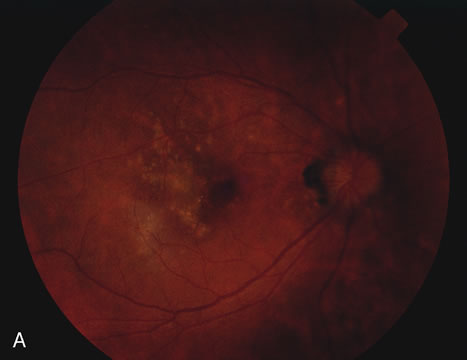

Acutely, there may be creamy white lesions in the posterior pole. These lesions tend to be deep and poorly demarcated. Sometimes these lesions may become confluent. The lesions clear by losing their yellow-white opacification and clearance occurs from centrally to the periphery. With time the lesions resolve leaving mottling of the retinal pigment epithelium (Figs. 5, 6, and 7).

Fig. 5. Fundus photograph showing the acute creamy lesions of a recent case of acute multifocal posterior placoid pigment epitheliopathy.

Fig. 6. Fundus photograph of the same case as in Figure 5. The findings at 1 month after the initial presentation now shows mild pigment clumping and mild retinal pigmentary atrophy.

Fig. 7. Fundus photograph of the same case as in Figure 5. The findings at 7 months following initial presentation show more pigment clumping and retinal pigment atrophy in small circular lesions.